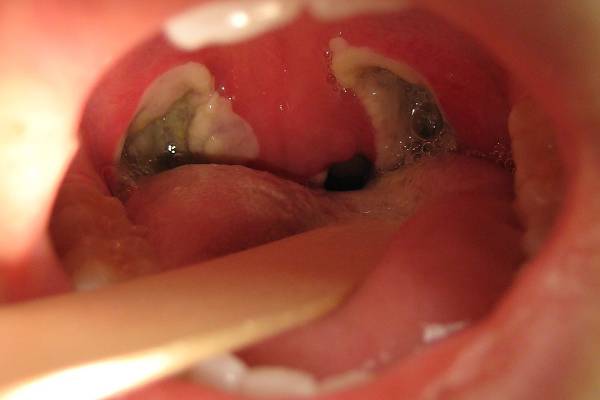

Coblation® Tonsillectomy

The technique uses gentle radiofrequency energy with a saline solution to quickly and safely